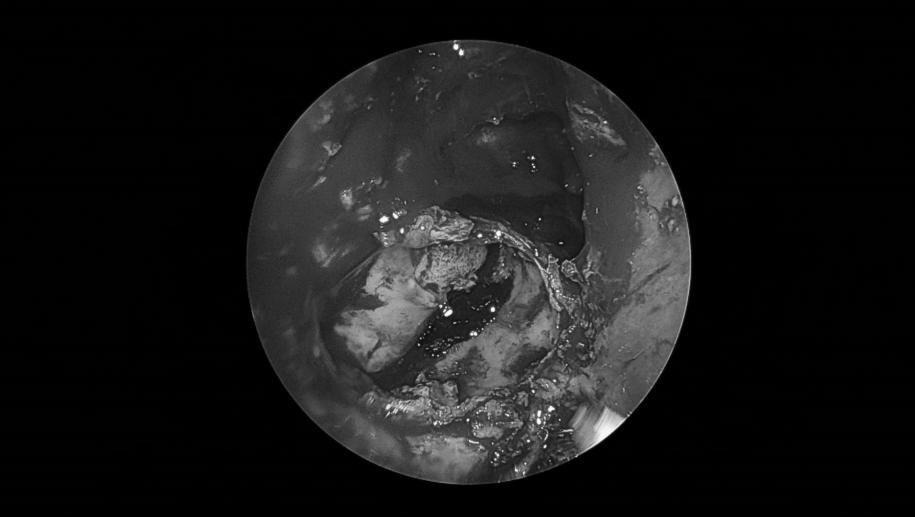

清除囊内病变后可见中颅窝底塌陷

(星号标示处)

切除部分囊壁,清除囊内病变,充分向鼻腔开放引流